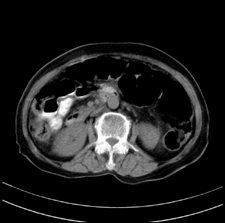

患者,女,75岁。腹痛,体黄5日,膝胸位时腹痛缓解。肝功能明日出来。彩超提示胆总管占位,未见血流信号。心电图提示s-t段改变。患者体质较弱,未能增强。

胆总管多发结石伴肝内外胆管轻度扩张。

胆总管上段,腔内有软组织密度影 ,ct值36-44hu。大家看有没有胆管癌的可能。

胆总管多发结石伴肝内外胆管扩张。

胆管没有鼠尾征,还是考虑结石

环形结石

胆管癌并结石。